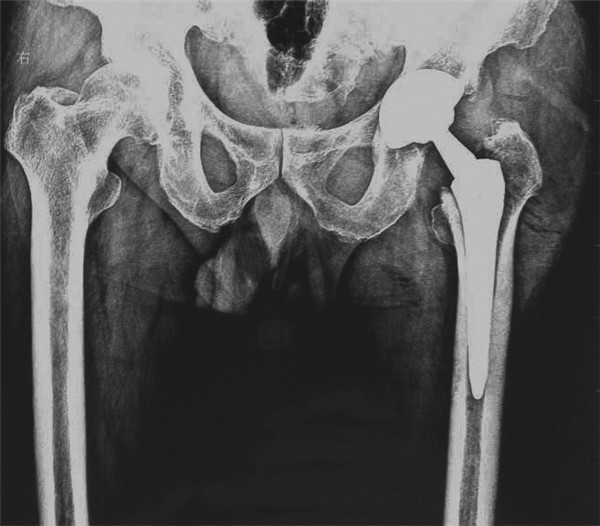

近日,由我院骨科王坤正教授带领王春生副教授、杨佩副教授、张子琦博士等人组成的优秀手术团队,在我院麻醉科手术科的全力配合下,完成了西北地区SuperPATH微创人工全髋关节置换术。手术过程非常顺利,患者术后康复状况良好。

微创全髋关节置换微创化是关节外科医生一直探索的目标。SuperPATH的出现,让我们真正看到了微创全髋关节置换时代的到来。并非切口越小就越微创,微创技术并不单单指切口的大小,切口小仅仅是微创手术的一个特点,而不是微创手术追求的唯一目标,如果片面地为了追求小的手术切口,过多损伤关节周围的肌肉、韧带,手术部位暴露不充分,致使手术假体安装的位置不准确,反而是因小失大,得不偿失,在保证手术部位得到充分显露的基础上,更重要的是保护关节运动所依赖的韧带和肌肉,尽量使切口越短越好。SuperPATH技术手术切口长度6cm--8cm;不需要切断外旋肌,经梨状肌和臀小肌的间隙进入,几乎保存髋关节周围所有的肌肉功能;几乎保留了完整的关节囊;手术操作过程中不需要外科脱位(术中不造成肢体极度的旋转与扭曲); 髋臼侧仅仅要求1cm的皮肤切口就可以完成。

该技术最大限度的维护了植入假体的稳定性,患者返回病房麻醉恢复后就可以下地自主行走,并在术后1月内就允许患者进行髋关节较大范围活动,这对于医患双方无疑是双赢的。